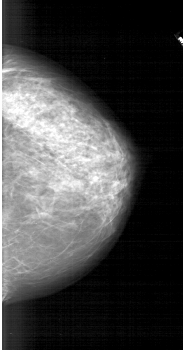

A_1744_1.RIGHT_CC

RIGHT_CC LINES 5941 PIXELS_PER_LINE 3106 BITS_PER_PIXEL 12 RESOLUTION 43.5 NON_OVERLAY